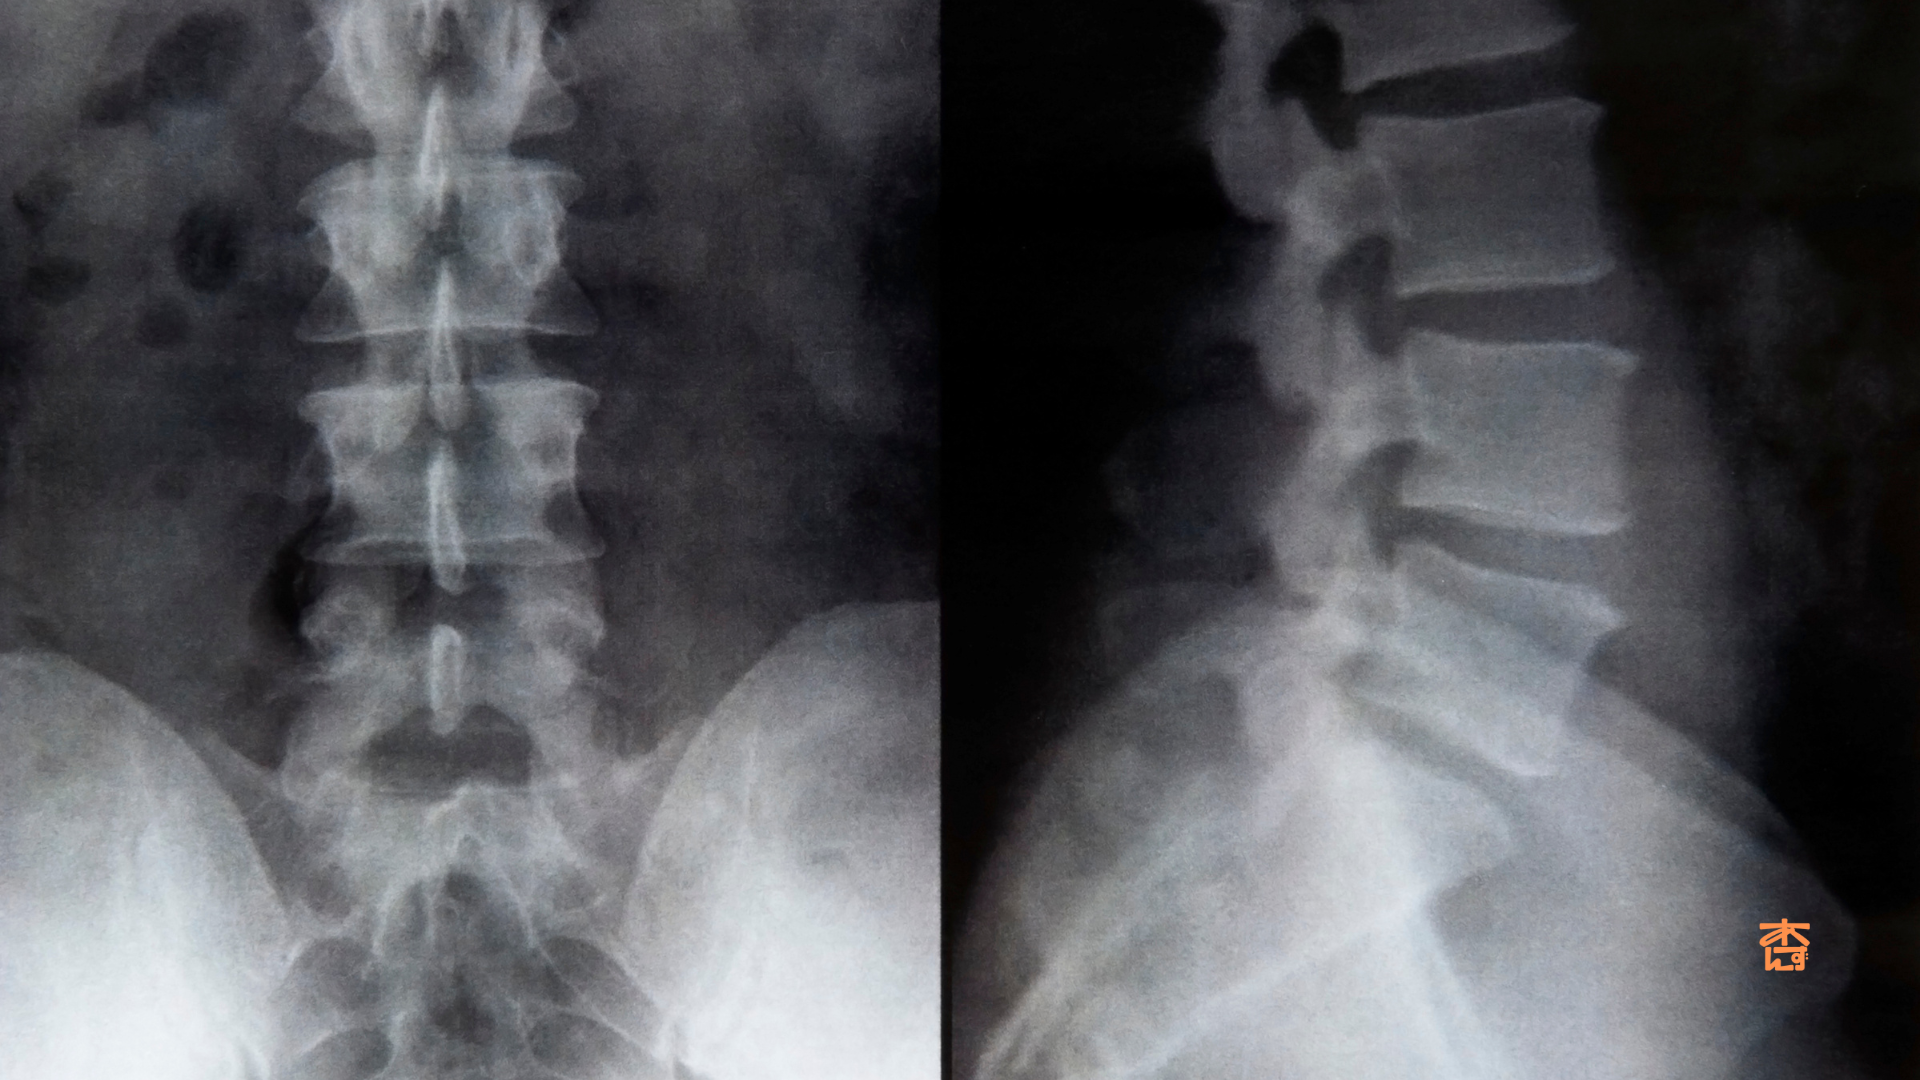

杏鍼灸整骨院での実際におこなっている施術

実際にLIPUSを照射している所です。